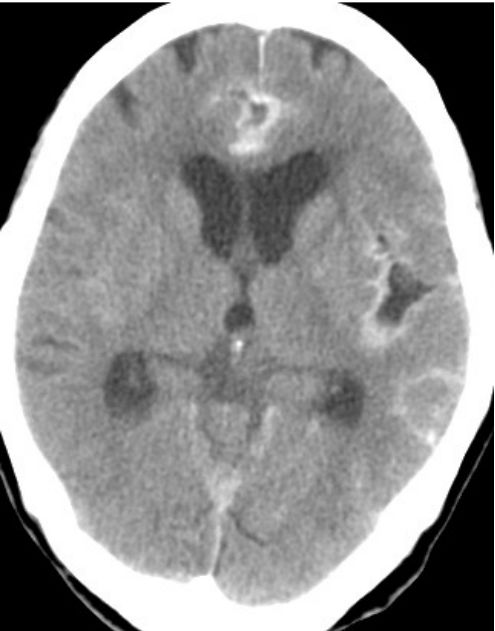

73.一位50歲女性,突發性劇烈頭痛被送到急診,電腦斷層發現蜘蛛網膜下腔出血(SAH),下列敘述何者最正確? (A)可安排電腦斷層血管影像檢查(CTA),以找出出血的病因 (B)可進行腰椎穿刺,以確定出血的原因 (C)惡性腫瘤出血是最常見的原因 (D)病患不會有水腦等症狀